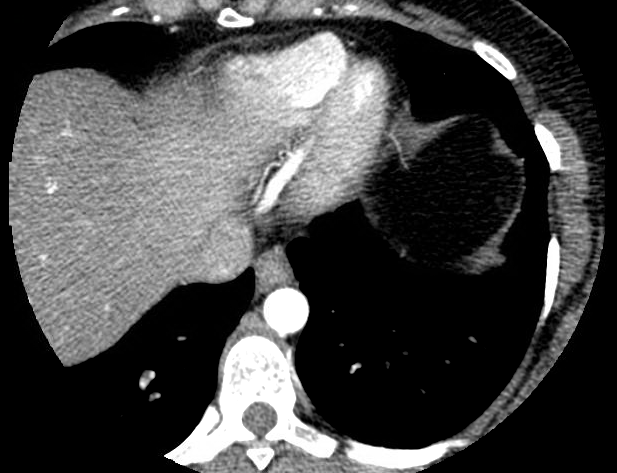

Case Presentation: A 32 year old female presented with 2 month history of acute onset pressure-like chest pain occurring after yelling at her children and radiating to the back. The symptoms recurred and become progressive while doing house chores. The pain was relieved by rest. Family history was positive for premature coronary artery disease, dyslipidemia and hereditary hemorrhagic telangiectasia. Examination revealed severe hypertension but no significant difference when taken from both arms. Laboratory data revealed negative troponin and ECG was without acute ischemic changes. Lipid profile showed elevated cholesterol. CT chest was unremarkable, however Coronary angiography CT showed tapering of the mid to distal left anterior descending coronary artery territory suggestive of coronary dissection. The coronary artery calcium score was 0.

Discussion: Spontaneous coronary artery dissection (SCAD) is defined as a non-traumatic and non-iatrogenic separation of the coronary artery walls, creating a false lumen and intramural hematomas leading to decreased blood flow and myocardial ischemia . It is an uncommon and poorly understood cause of acute coronary syndrome (ACS), myocardial infarction and sudden cardiac death. SCAD is a rare cause of acute coronary syndrome with incidence of 0.04% to 0.2% of coronary angiographies. It is associated with sudden death in 50% of cases. 75% of affected patients are female, with an average age 40 years old at the time of diagnosis.

Coronary angiography allows for early diagnosis of SDCA. More than 80% of acute SCAD patients are treated medically with standard medical therapy as in ACS. Only 3.3% require revascularization. Our patient had a good clinical outcome on medical treatment alone.